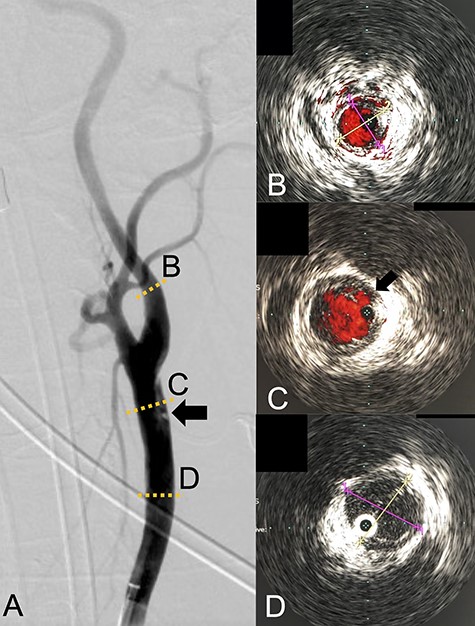

We performed CAS and started dual antiplatelet therapy 27 days after stroke onset to prevent further dissection and cerebral infarction recurrence. The dissection started 1.5-cm below the carotid bifurcation (Fig. 3A). An 8 fr guiding catheter (FlowGate2 Balloon Guide Catheter, Stryker, Fremont, CA, USA) was positioned at the proximal portion of the left CCA with a micro-guidewire (ASAHI CHIKAI Black, Asahi-Intecc, Nagoya, Aichi, Japan) crossing the dissected lesion. A distal protection device (SpiderFx Embolic Protection Device, Medtronic, Minneapolis, MN, USA) was deployed at the petrous portion of the ICA. IVUS was first advanced into the petrous ICA, and vessel wall imaging was performed by slowly withdrawing the device. IVUS imaging confirmed the existence of the dissection’s pseudo-lumen starting 1-cm proximal to the carotid bifurcation (Fig. 3C). IVUS provided the ICA and CCA diameters, which helped decide the most suitable stent (Fig. 3B and C). To adequately cover the dissection lesion, we placed two opened cell stents (Protégé, Medtronic, Minneapolis, MN, USA); one was an 8–6-mm tapered model with a length of 40 mm to cover the lesion from the distal CCA end to the proximal portion of ICA. Another was a 10-mm straight model with a length of 40 mm covering the CCA. Post-dilation was performed SterlingTM Balloon Dilation Catheter (Boston Scientific, Natick, MA, USA) with 5 × 20 mm covering both stents’ edges. The final angiography showed successful treatment with a smooth intra-arterial lumen (Fig. 4A). IVUS imaging showed sufficient stent coverage of the entire dissection lesion. It also confirmed a good expansion of the stent to the dissection area’s arterial wall with no plaque protruding the stents (Fig. 4B).

Angiography revealed the dissection starting proximal to the carotid bifurcation (Black arrow: A). IVUS provided the diameters of the ICA and CCA (B and D, respectively). IVUS imaging confirmed the pseudo-lumen of the dissection starting 1-cm proximal to carotid bifurcation (C) and the entry point of the dissection as well (Black arrow: C).

We would further like to note the usefulness of IVUS in this particular case. IVUS clearly visualized both the dissection’s entry point and the blood flow from true- to pseudo-lumen, the information of which is essential for treatment strategy planning. IVUS also provided helpful information to assess the stent’s coverage (Fig. 3). IVUS allowed us to predict the entire length of the arterial dissection before stent deployment [11]. Furthermore, IVUS provided important information for stent-size selection. Although the pseudo-lumen caused by the dissection made it difficult for us to precisely measure the true lumen diameter, IVUS allowed us to measure the diameter of the true lumen of the dissected artery, and we were able to select the appropriate stent for treatment. It also provided helpful information that proper stent apposition was established even after the stent deployment and post-balloon dilation, which indicated no additional angioplasty was necessary.